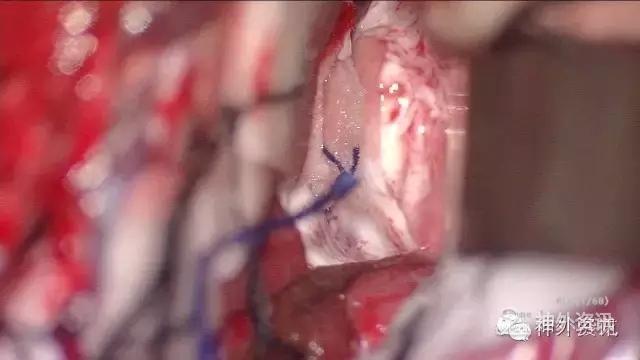

MRI:右侧丘脑占位,考虑胶质瘤可能性大(Ⅲ-Ⅳ级),病灶累及中脑右侧大脑脚,轻度脑积水;不除外转移瘤可能,请结合相关病史及检查。

初步诊断:丘脑占位,胶质瘤可能。

影像学检查: